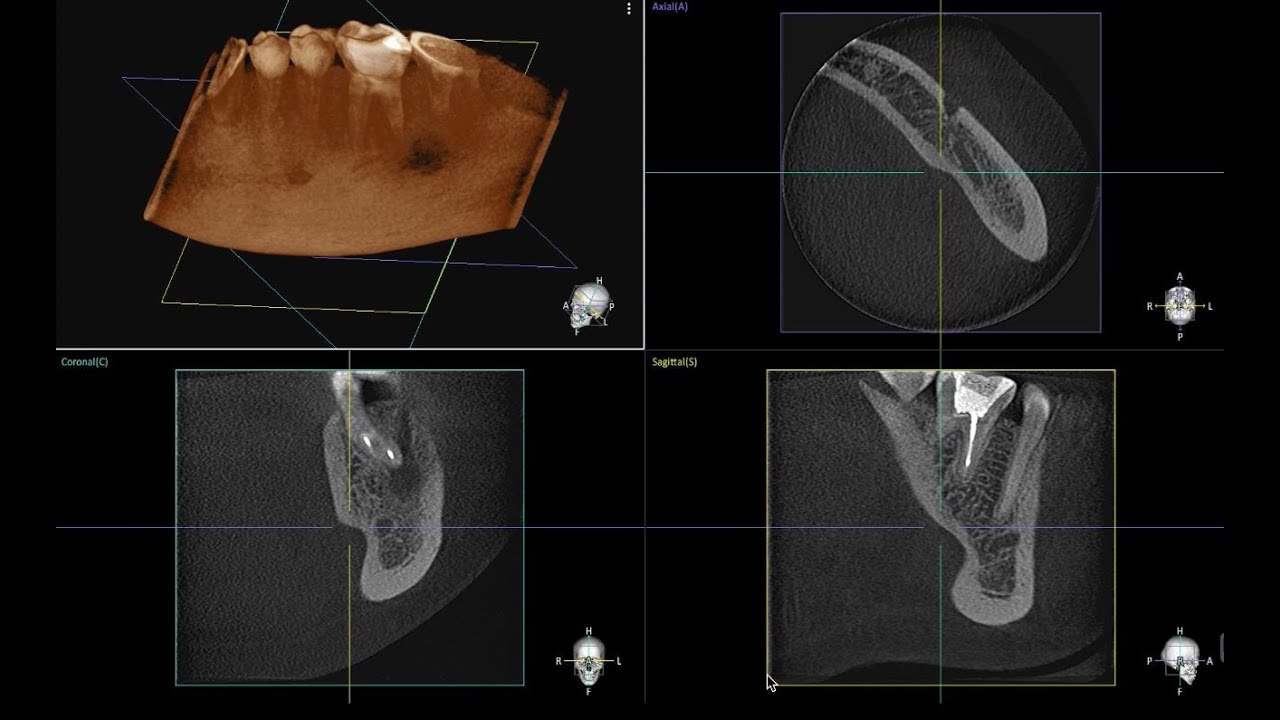

• Tomografi görüntüleri ile Kasti Reimplantasyon

Tomografi görüntüleri ile Kasti Reimplantasyon